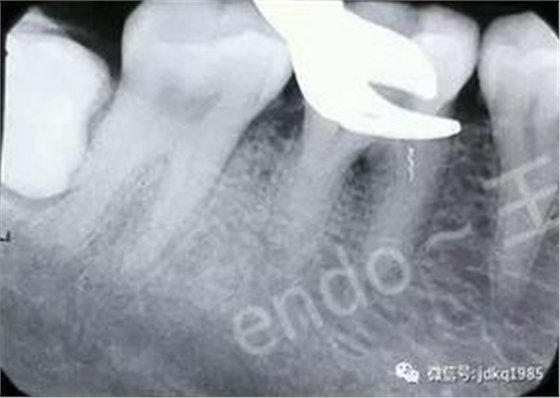

顯微鏡下在根管口可見(jiàn)斷針上端

應(yīng)用專用的“取斷針”器械盒,在顯微鏡輔助下建立直線通路,游離斷針